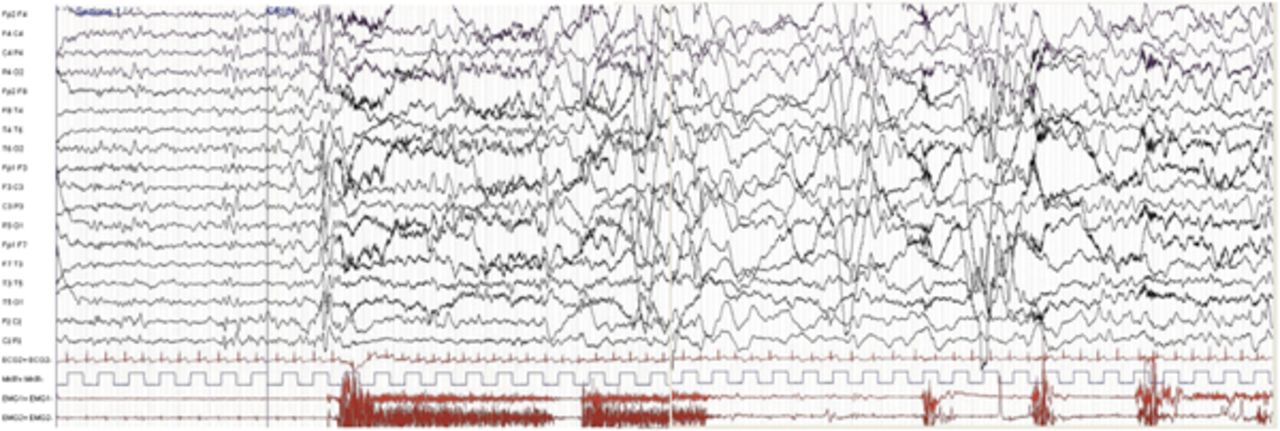

8年,岁的癫痫的临床和脑电图的发现暗示脑病(图1和图2)。女孩继续呈现多个每日发作逐渐恶化的神经认知方面。认知水平恶化轻度精神发育迟滞,随后的赤字严重的学习。此外,她还出现共济失调。在眼科检查,发现视网膜下drusen-like存款有斑点的视网膜。为了更好地研究她的视网膜有斑点的方面,我们执行一个网膜电图和视觉诱发电位,这是正常的。